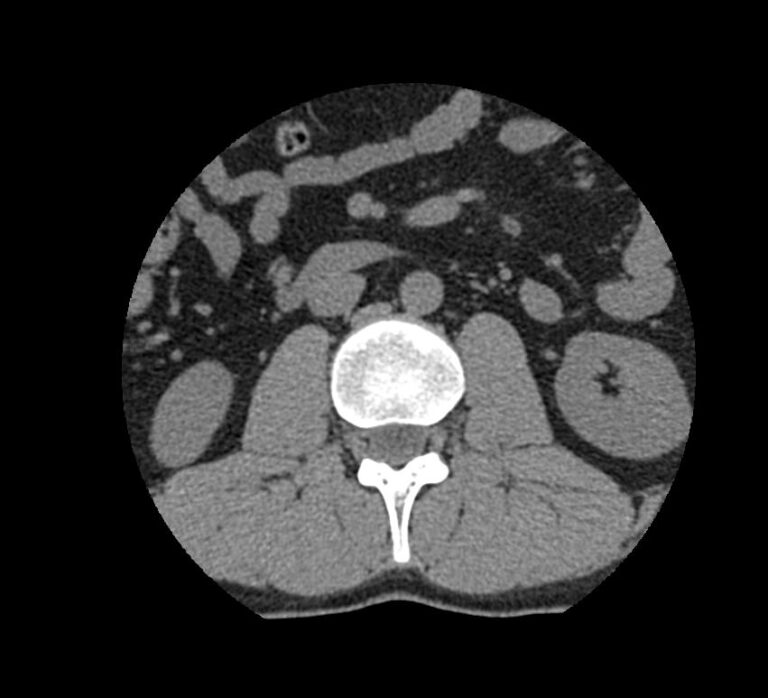

Мультиспиральная компьютерная томография является наиболее точным и информативным методом диагностики различных заболеваний позвоночника и, в частности, пояснично-крестцового отдела. Сканирование проводится при помощи рентгеновского излучения, в результате чего получают серию послойных изображений пояснично-крестцового отдела позвоночника.

В медицинских центрах «Доступная медицина» обследование пояснично-крестцового отдела позвоночника осуществляется на современных мультиспиральных компьютерных томографах последнего поколения TOSHIBA AQUILION в модификациях, позволяющих выполнять одномоментно 64 и 128 срезов анатомической зоны для получения снимков высокого разрешения. Послойное сканирование исследуемой области проводится с минимальной толщиной среза от 0,5 мм, что обеспечивает получение изображений органов в мельчайших подробностях.

Инновационные компьютерные приложения позволяют построить 3D-модель исследуемого органа, обеспечивая детальную визуализацию строения внутренних структур позвонков, хрящевых элементов, кровеносных сосудов и окружающих тканей.